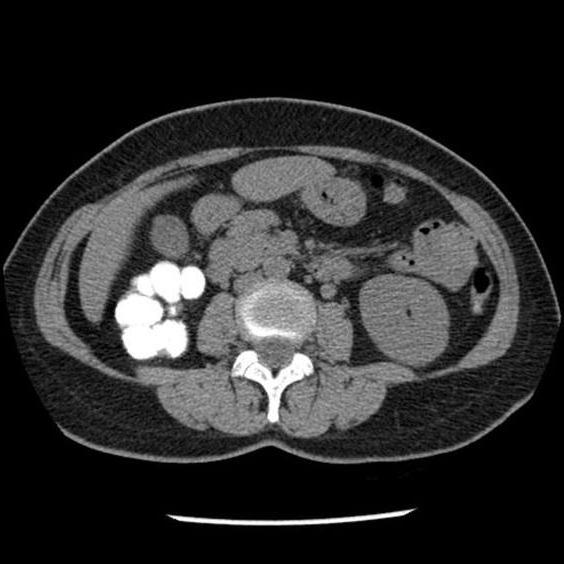

Стоит отметить, что абдоминальные поражения встречаются редко и составляют всего 2-3% от всех случаев внелегочного туберкулеза. Как правило, сначала патологический процесс охватывает лимфатические узлы забрюшинноого пространства и брыжейки и только после этого туберкулезные поражения распространяются на органы брюшной полости.

Стоит сказать, что иногда недуг может переходить на пищевод. В таких случаях наблюдается постепенное изъязвление стенок пищеводной трубки, ее сужение вплоть до полного стеноза. Примерно такая же картина наблюдается и при поражении желудка — в пилорическом отделе и в области большой кривизны образовываются небольшие, но множественные неболезненные язвы.

Поражение кишечника может переходить на ткани червеобразного отростка. Иногда у пациентов диагностируется и туберкулез тонкого кишечника. К сожалению, выявление внелегочного туберкулеза в данном случае является трудным процессом. Симптомы заболевания не слишком выражены, а клиническая картина нередко напоминает хронические энтериты, аппендициты и прочие заболевания органов пищеварительной системы.

К опасным формам туберкулеза относится мезаденит. При подобном недуге поражаются лимфатические сосуды брюшины, но процесс постепенно переходит на матку и яичники. Фиброзный воспалительный процесс органов репродуктивной системы становится причиной бесплодия у пациенток.

Туберкулезный перитонит

Туберкулезный перитонит — самая распространенная форма воспаления брюшины или брюшной полости хронического характера.

- Нарушения аппетита.

- Слабость.

- Быстрая утомляемость.

- Головные боли.

- Перепады настроения.

- Повышенная потливость.

- Неприятные ощущения в животе.

- Нарушение стула (жидкий стул / запор).

- Может наблюдаться рвота.

- Тянущие боли в области живота.

- Ощущение вздутости живота.

- Нарушение обмена веществ (быстрое снижение веса, либо его набор).

- Эмоциональные всплески или инертность.

- Нарушение менструального цикла у женщин.